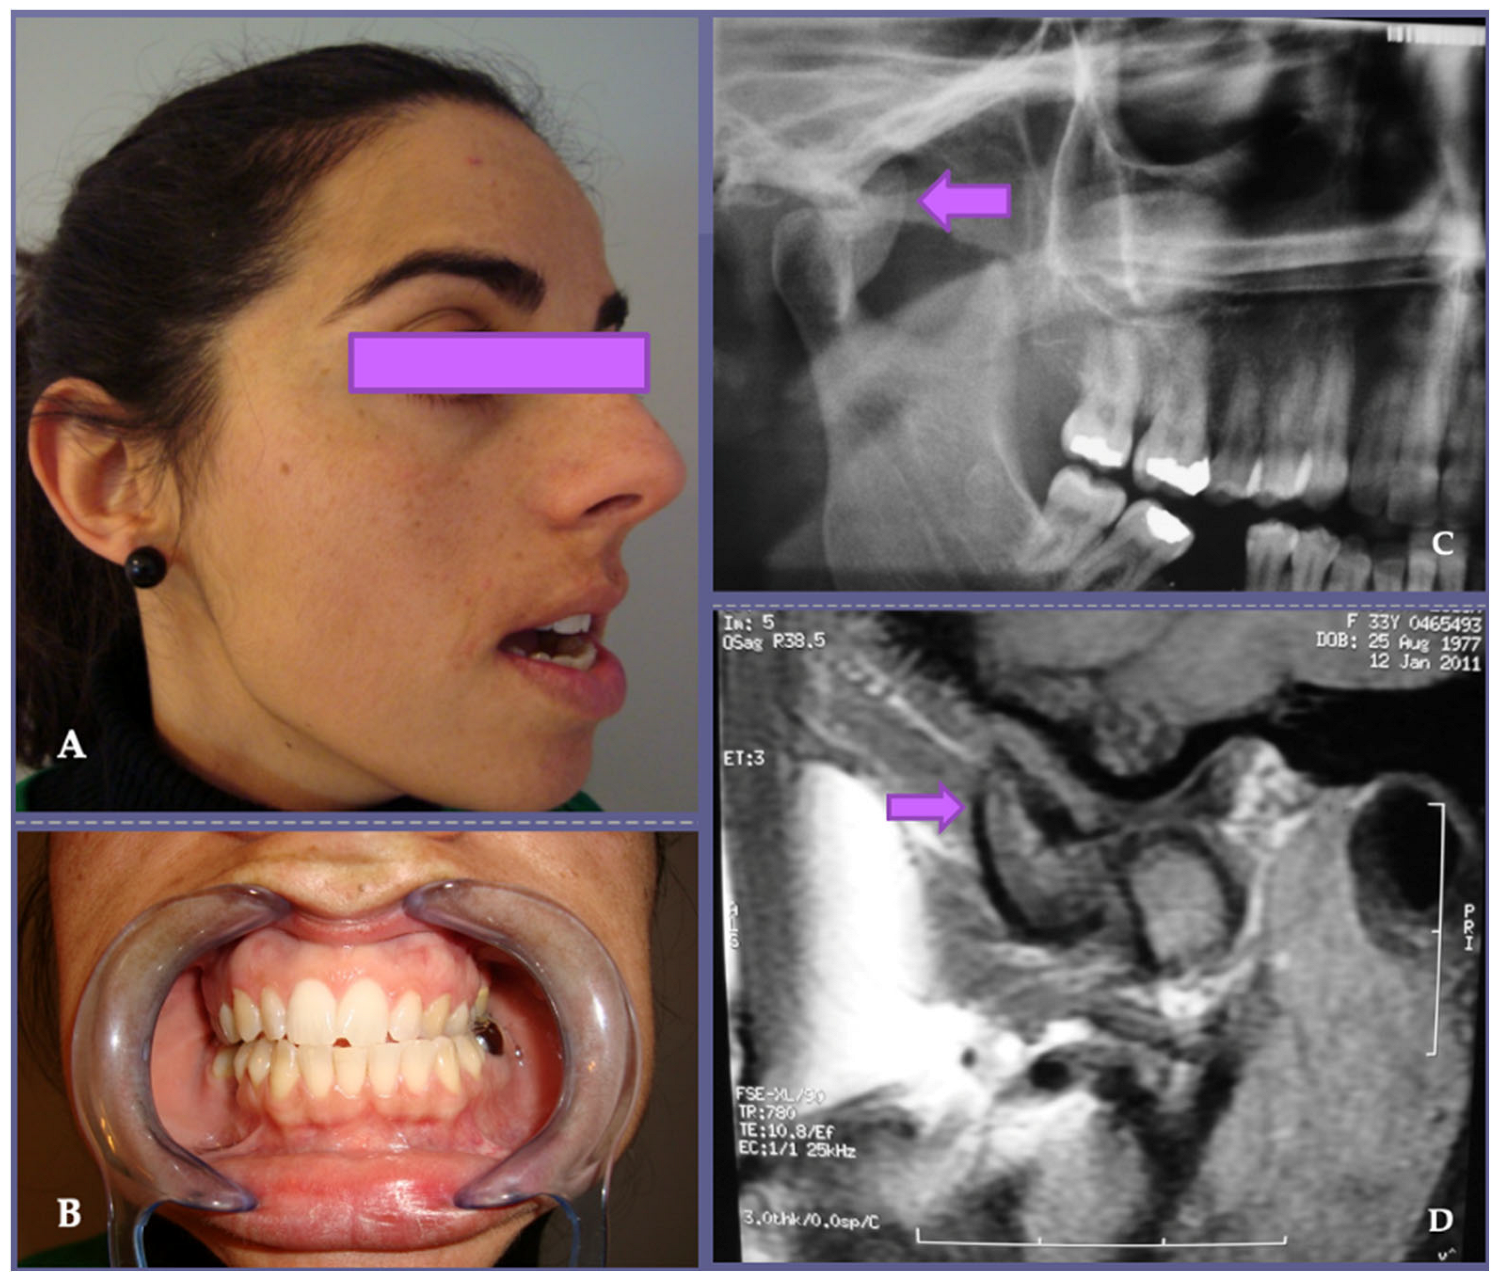

| 14 | 30/F | TMJ dysfunction | Mottled densities | 6 | 2 | 4.3 | 5 | Osteochondroma | Right |